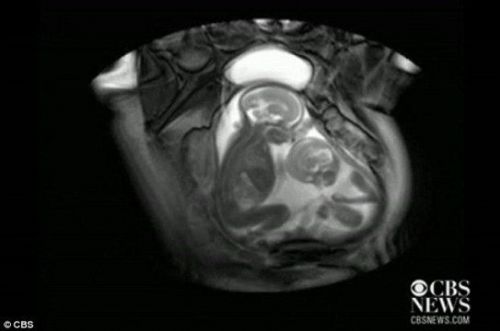

核磁共振成像技术显示,一对双胞胎在妈妈肚子里拳脚相向“掐架”

中新网12月1日电 据外媒报道,近日一段对孕期20周孕妇的核磁共振的扫描视频显示,一对双胞胎还在妈妈肚子里就开始挥动手脚 “掐架”,令人感到神奇又搞笑。

据报道,英国伦敦帝国理工学院(Imperial College)胎儿保健中心本打算用核磁共振成像仪来诊断共享一个胎盘和同一个血液供应系统的胎儿双胞胎输血症候群(twin transfusion syndrome)情况,却意外拍到了子宫中双胞胎的“大战”。

视频显示,画面右边个子稍小的胎儿在对左边稍大的胎儿挥动手脚,“拳打脚踢”,似乎打算用身体争得更多空间。而后者比较安分,也动了动嘴,缩了一下身子。